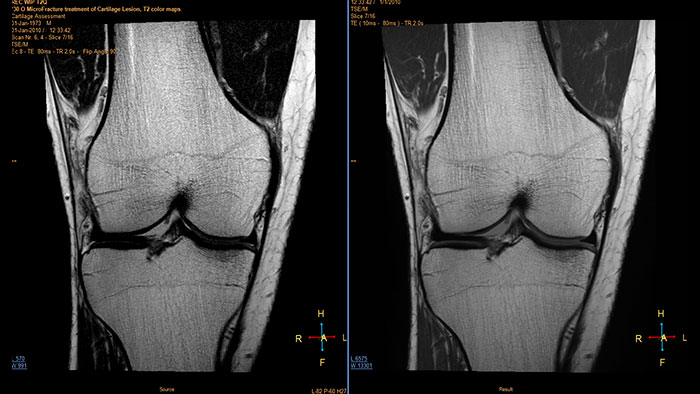

MR Cartilage Assessment

Visualize cartilage structures

Enables the visualization of cartilage structures integrated with color-coded T2 maps. Positioning of cartilage-shaped, layered region of interest is used to assess variation of T2 values across the cartilage depth to determine the degradation of the cartilage.

Benefits

- The MR Cartilage Assessment application features a task-guided workflow for the quantitative analysis of T2 relaxation time to support cartilage assessment and disease status.

- The application provides segmentation tools, allowing measurements of cartilage layers and segments.

- T2 values are numerically and graphically displayed per layer and segment.